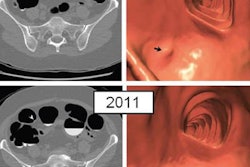

More than 20% of polyps detected at CT colonography (CTC) may be missed at subsequent optical colonoscopy, according to a study in Radiology. What's more, most of the missed polyps were large and clinically significant.

Researchers from the University of Wisconsin in Madison performed CTC (also known as virtual colonoscopy) in nearly 10,000 adults, reviewing more than 1,600 polyps for which patients underwent subsequent optical colonoscopy to confirm positivity. Among the lesions that showed up on one exam but not the other, 21.5% were confirmed as false negatives at optical colonoscopy, with an average size of 8.5 mm in diameter.

In the current study, 9,336 adult patients (4,210 men, 5,126 women; mean age, 57.1 years) underwent a total of 10,976 screening CTC exams. CTC detected 2,606 polyps that were 6 mm or larger. Unblinded optical colonoscopy was then performed for 1,607 of the 2,606 polyps, while 74 patients had flexible sigmoidoscopy and 50 patients went directly to surgery. The remaining 875 polyps received CTC surveillance.

Of the 1,731 polyps that underwent endoscopic or surgical follow-up, 181 (10%) were not confirmed and were therefore considered discordant; 37 of these were later excluded. After a polyp review, 66 of the 144 lesions were categorized as probable CTC false-positive findings, and 78 were categorized as potential colonoscopy false-negative findings.

In all, 31 (21.5%) of the 144 discordant lesions were confirmed as false negatives at optical colonoscopy, including 40% (31 of 78) in patients who had optical colonoscopy and/or CTC follow-up, the authors reported.

False-negative optical colonoscopy lesions measured an average of 8.5 ± 3.3 mm and were found at higher confidence levels at CTC (2.8 versus 2.3 on a scale of 1 to 3, p = 0.01). Lesions missed at optical colonoscopy were also more likely to be located in the right colon (71% versus 47% in the left colon, p = 0.10).